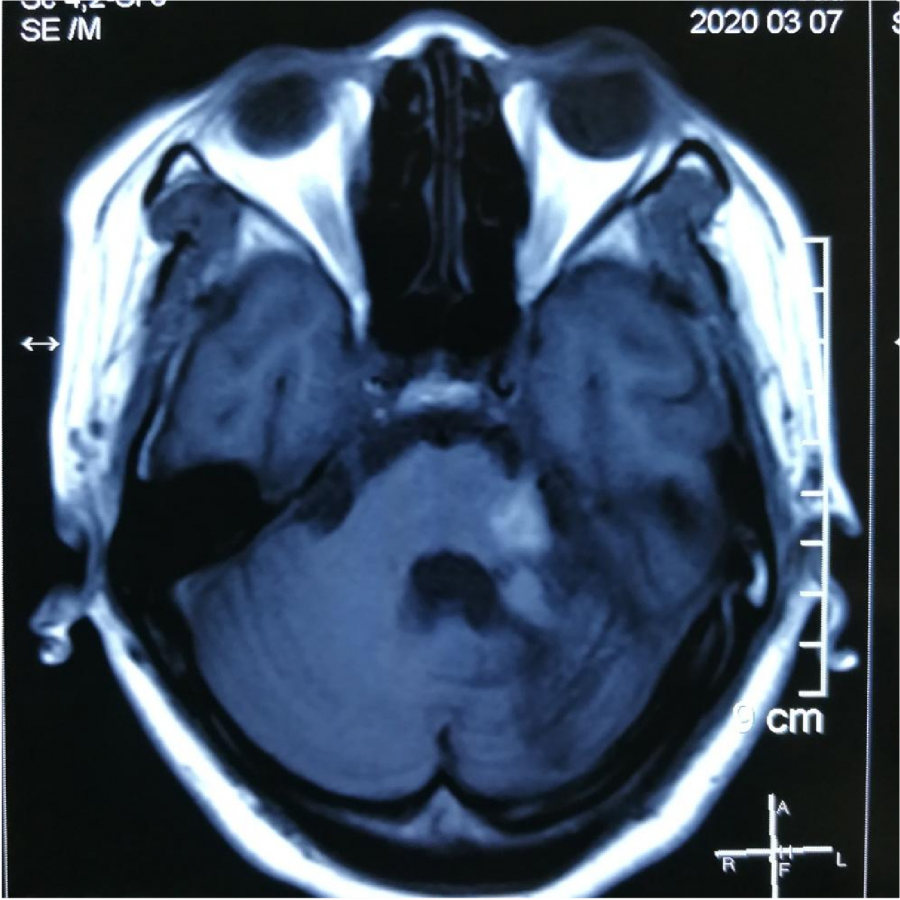

MR显⽰桥脑左侧⾼信号影

小脑及脑⼲受累